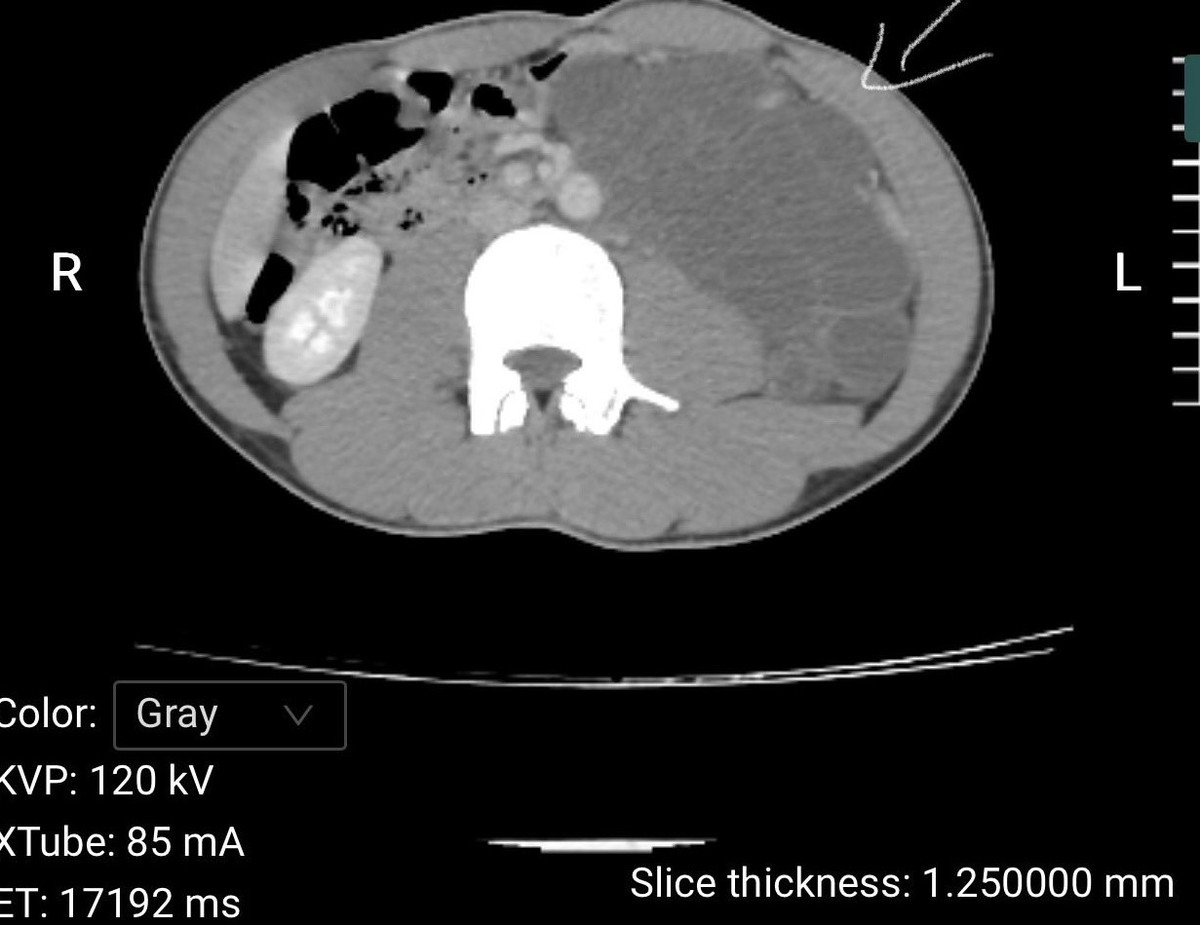

Các bác sĩ khoa Ngoại tổng hợp, Bệnh viện Đa khoa số 3 tỉnh Lào Cai vừa phẫu thuật thành công cho bệnh nhân L.V.Đ., 25 tuổi, quê Nậm Có – Lào Cai, mắc u Lymphangioma sau phúc mạc rất lớn biến chứng chèn ép tạng, một bệnh lý hiếm gặp và phức tạp.

Tại Bệnh viện Đa khoa số 3 tỉnh Lào Cai, sau thăm khám và chụp chiếu, làm các xét nghiệm cận lâm sàng, các bác sĩ chẩn đoán bệnh nhân mắc: U sau phúc mạc bên trái.